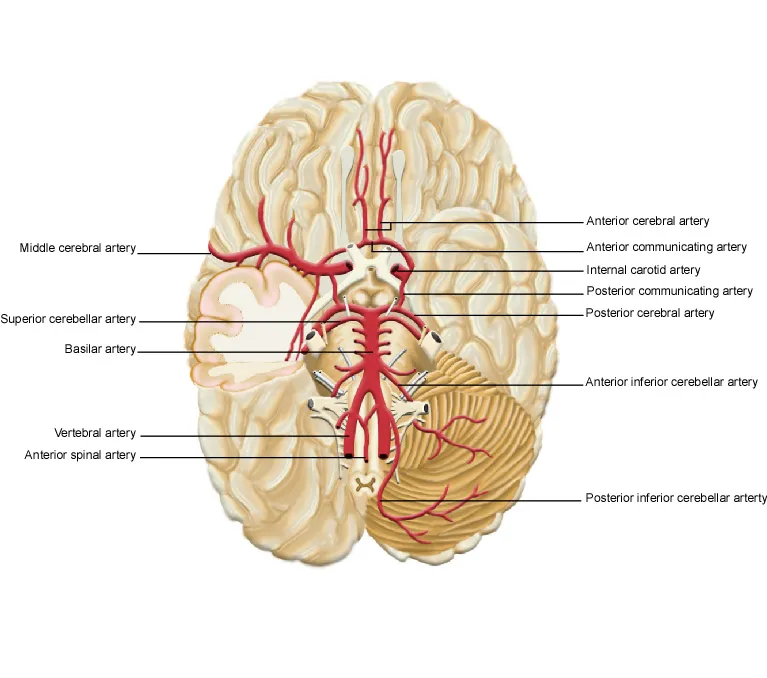

The internal carotid system supplies 80% of cerebral blood flow through anterior and middle cerebral arteries:

Anterior Cerebral Artery (ACA) Territory

Middle Cerebral Artery (MCA) Territory

MCA strokes produce the most common cerebrovascular syndromes:

| MCA Division | Territory | Clinical Syndrome | Frequency |

|---|---|---|---|

| Main Stem | Entire MCA territory | Complete MCA syndrome | 15% of MCA strokes |

| Superior Division | Frontal-parietal | Broca's aphasia, arm weakness | 35% of MCA strokes |

| Inferior Division | Temporal-parietal | Wernicke's aphasia, visual field cut | 25% of MCA strokes |

| Lenticulostriate | Basal ganglia | Pure motor hemiparesis | 20% of MCA strokes |

| Cortical Branches | Specific gyri | Focal deficits | 5% of MCA strokes |

The vertebrobasilar system supplies 20% of cerebral blood flow to posterior brain regions:

Posterior Cerebral Artery (PCA) Territory

Vertebrobasilar Territory

Watershed areas represent vascular borderlands susceptible to hypoperfusion:

Cortical Watersheds

Subcortical Watersheds

| Vascular Territory | Blood Flow | Clinical Deficits | Collateral Potential |

| ACA | 250 ml/min | Leg weakness, abulia | Good via AComA |

| MCA | 400 ml/min | Hemiplegia, aphasia | Limited leptomeningeal |

| PCA | 100 ml/min | Hemianopia, memory loss | Moderate via PComA |

| Vertebrobasilar | 200 ml/min | Brainstem signs, ataxia | Poor end-artery supply |

Cerebral venous drainage follows predictable patterns with clinical implications:

Superficial Venous System

Deep Venous System

💡 Master This: Vascular territory knowledge enables rapid stroke localization - deficit pattern immediately suggests arterial involvement and guides acute intervention timing.

Understanding cerebrovascular anatomy transforms stroke evaluation from symptom description to precise anatomical localization and targeted therapeutic intervention.